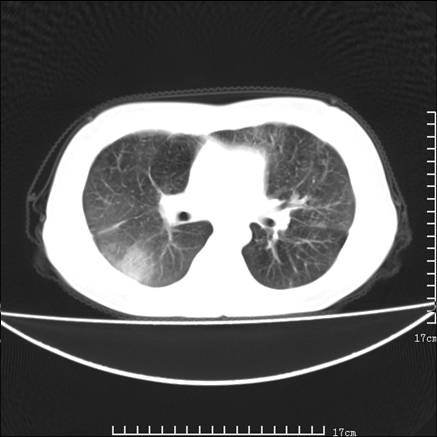

女,46岁,患胃溃疡多年,溃疡大小约1.0cm左右,后于5年前手术,病理为胃癌。主诉:半月前感冒后胸闷,气短,有咳嗽,无明显咳痰,无发热。偶有腰背部不适。

以下为高分辨扫描图像

双肺小叶间增厚,双肺散布粟米影和磨玻璃状影,以双肺上叶为重。结合病史考虑转移(癌性淋巴细管炎)可能性大。

正如caihe主任所言,影像表现结合临床病史应该支持肺癌性淋巴管炎;上肺大片边缘不清的渗出病变,多系感染所致,临床有感冒病史并咳嗽表现。肺癌性淋巴管炎临床一般无咳嗽、咳痰症状。

鉴别:

1、结节病,多位于肺的上中部和后部,呈向心性分布,造成近肺门区的支气管血管束周围间质和胸膜下间质增厚,小叶间隔增厚不明显,即使增厚也较为局限

2、尘肺,可以通过病史,肺外周为主的多发结节,胸膜假斑,聚合成的团块,间质纤维化等鉴别

3、肺水肿,肺水肿可以造成肺间质的增厚,为光滑的增厚且常为双侧对称性分布。